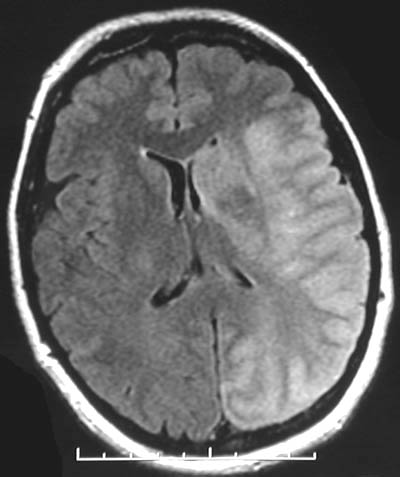

| The MRI scan in FLAIR mode above and enhanced below reveals an area of massive infarction of the left cerebral hemisphere, mostly in the right middle cerebral distribution, that is of recent formation, with brain swelling and a midline shift to the right compressing the ventricular system. |